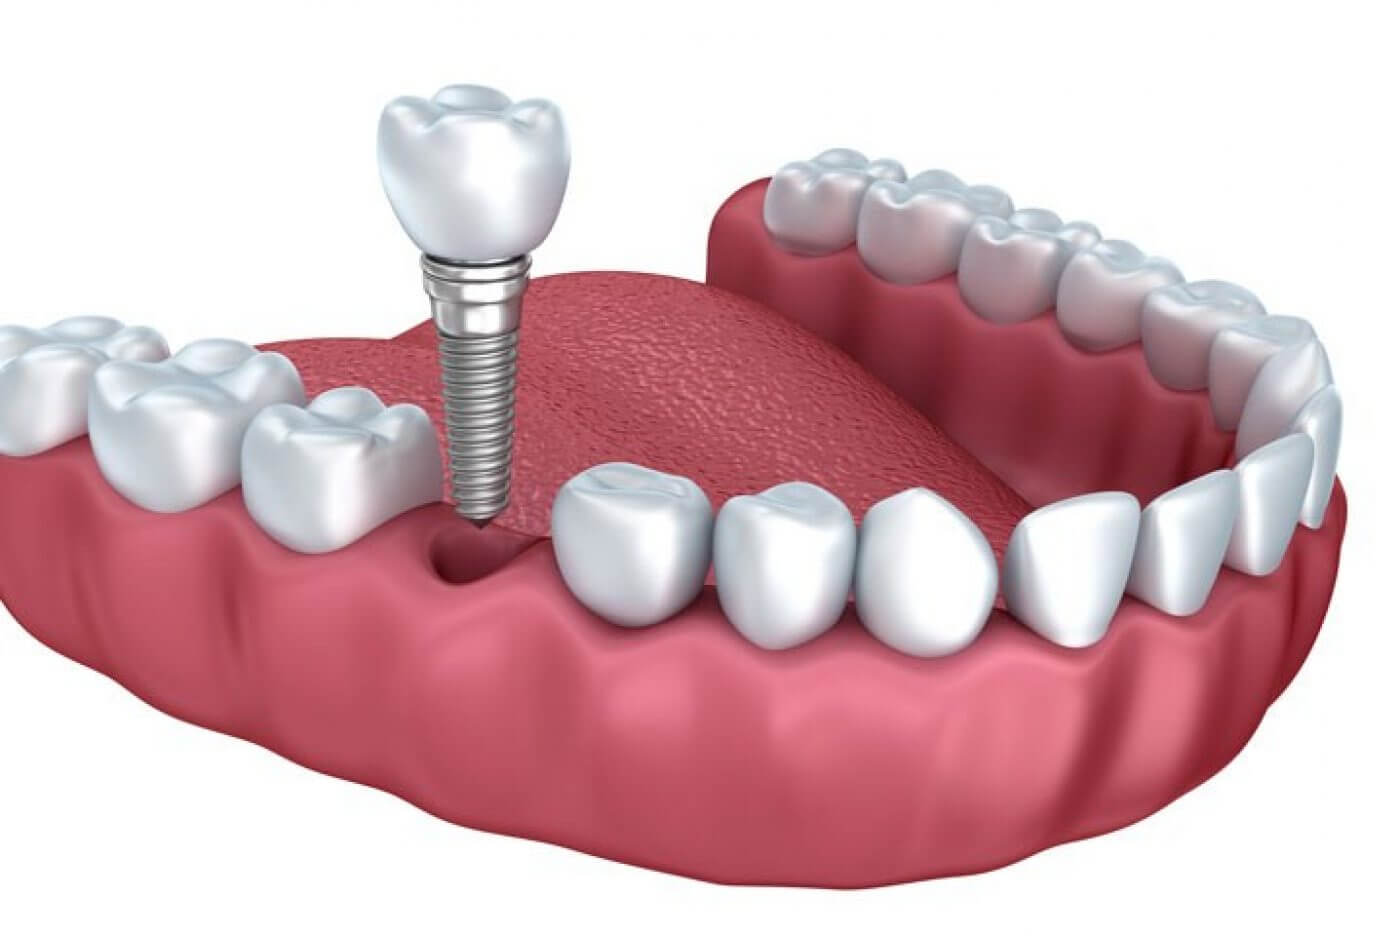

İmplant

İmplant tedavisi; dokularla biyouyumlu, diş kökünü taklit eden yapay diş kökü titanyum yapıların çene kemiğine yerleştirilmesidir. Diş eksikliği nedeniyle gerek estetik, gerekse fonksiyon kaybı yaşayan hastaların öncelikli tercihi olan vidalı dişler, titanyum denilen doku dostu bir materyalden üretilmektedir.

Hastaların sistemik sağlık durumlarının değerlendirilmesi, ağız içi muayenesinin dikkatle yapılıp, gerekli 3 boyutlu radyografik kontrollerin ve ölçümlerin yapılmasının ardından hastanın tedaviye uygun olup olmadığına karar verilir. Başarılı bir implant operasyonu' nun gerçekleşmesi için implantın uygulanacağı bölgenin kemik yapısının olması ve diş etlerinin de oldukça sağlıklı olması gerekir.

Hastaya kaç implant yapılacağına tamamen hastanın ağız muayenesi yapıldıktan sonra ve filmine bakılarak karar verilmektedir. Planlama yapılırken, hastada kaç dişin eksik olduğu, hastanın kemik yapısı, dişlerin kapanışının nasıl olduğu, implant yapılacak bölgenin estetik ihtiyacı gibi birçok başlığın değerlendirip ona göre karar verilmesi gerekmektedir.

İmplant operasyonu lokal anestezi altında yapılır. Tedavi, uygulama alanının uyuşturulması ile başlar. Bu implantlar diş doktorları tarafından ufak bir cerrahi işlem ile çene kemiğinize yerleştirilir. Kemik ile osseointegrasyon kaynaşmasını beklemek yaklaşık 3-6 ay kadar sürmektedir. Ancak, çene kemiğinin yetersiz olduğu hastalarda kemik tozu (greft) gibi çeşitli yöntemlerle kemik kalınlaştırılmasının yapıldığı hastalarda bu süreç daha uzun olabilmektedir. Bu noktadan sonra implantlar gerçek bir diş kökü gibi olur. Bu bekleme süresinin ardından gerekli kontroller sağlandıktan sonra protez tedavisi yapılmaktadır.